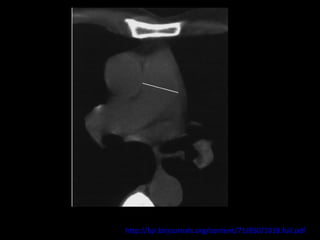

Achados de imagem: Rx e TC

Artérias pulmonares centrais dilatadas;

Trombo ocluindo e reduzindo o diâmetro da artéria

ocluída;

Localização excêntrica dos êmbolos pulmonares

com ou sem calcificações;

Estreitamento abrupto do diâmetro arterial;

Recanalização das falhas de enchimento

intraluminal;

Dilatação das artérias brônquicas.